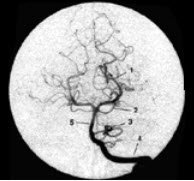

分别标出如图所示1_______________2_______________3_____________4______________5_______________为颅内哪根血管。